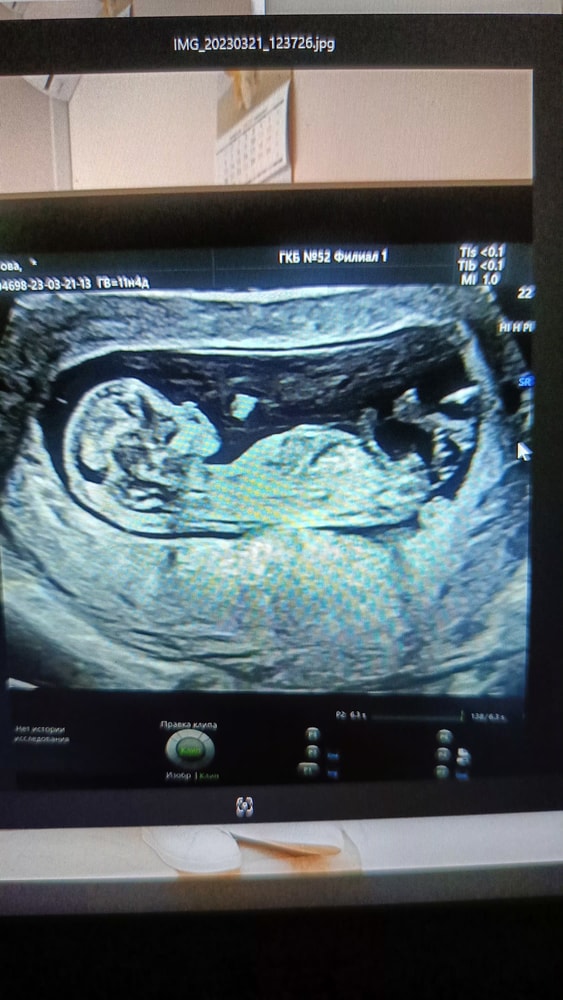

Это просто зависит от ракурса, узист выводит на экран то, что ему нужно. УЗИ же и работает так, чтобы нужные ткани показывать, как бы через слои проникать. У меня на фото с первого скрининга тоже нет ручек и ножек, но на самом УЗИ детёныш так ими размахивал, что не увидеть их было сложно. На нескольких фото с УЗИ у него рука во рту, видна хорошо. А ручки, которая ближе к датчику, не видно. Это 17 недель. Изображение Или вот, например, 15-недельная пятка. Тоже в воздухе висит, без остального тела. Изображение